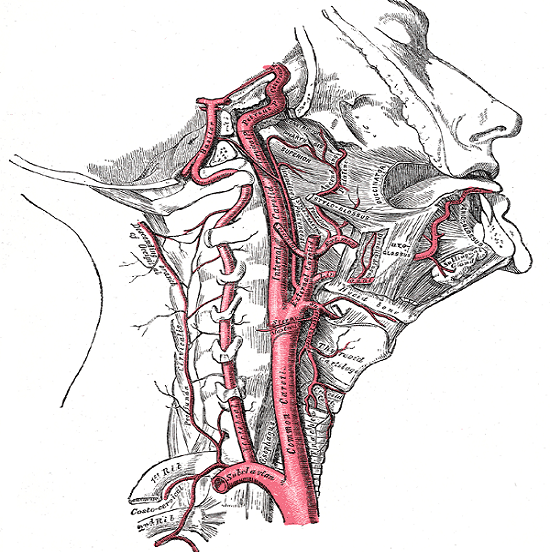

Общая сонная (каротидная) артерия является парной. Это означает, что одинаковые сосуды имеются с левой и с правой стороны. Левая — начинается от дуги аорты, а правая — от брахиоцефального ствола. Направляясь вертикально вверх, они минуют грудную клетку и выходят в область шеи. Далее ход и строение не отличаются, поэтому будем анатомические особенности рассматривать на примере одного сосуда.

Ствол идет под грудино-ключично-сосцевидной мышцей рядом с пищеводом и трахеей. Над верхним краем щитовидного хряща он делится на наружную сонную артерию и внутреннюю. Это место называется бифуркацией. Сразу после ответвления внутренняя сонная артерия образует небольшое расширение (каротидный синус). Он покрыт многочисленными нервными клетками, является важной рефлекторной зоной.

Особенности наружной ветви

Ветви наружной сонной артерии снабжают кровью:

- большую часть лица (мышцы, кожу головы);

- ухо;

- язык;

- корни зубов;

- щитовидную железу;

- часть твердой мозговой оболочки;

- глазное яблоко.

Одна из важных функций — возможность обратно направленного кровотока для оказания помощи ветвям внутренней сонной артерии и позвоночной при их сужении. В таких случаях кровь по анастомозам поступает в базиллярную, а через глазничные ветки — во внутреннюю каротидную.

Особенности внутренней ветви

Внутренняя ветвь сонной артерии входит в череп сквозь специальное отверстие в височной кости. Такое расположение называют интракраниальным. Ее диаметр равен 10 мм. В области основания мозга совместно с позвоночными сосудами (базальная артерия) через анастомоз с задними мозговыми артериями образует виллизиев круг. Это главный источник кровоснабжения мозга. От него отходят артерии вглубь извилин, к белому и серому веществу, ядрам продолговатого мозга и корковым центрам.

Ветви наружной артерии близко подходят к мышцам, по ней можно считать пульс